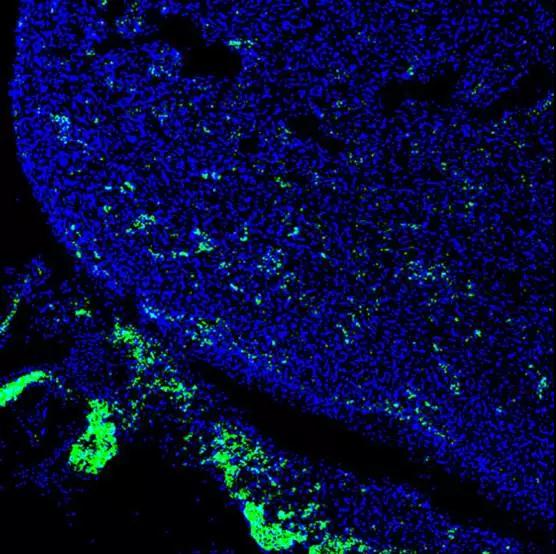

在4周大的嵌合猪胚胎中,人类细胞呈绿色显示在这颗发育中的心脏(图片来源 STAT)

但显而易见,在猪身上培育人体器官还有很长很长的路要走。而这一切在CRISPR的“横空出世”之后,研究似乎变得明朗起来。2017年1月,该研究团队在《Cell》杂志上发文称,将人类干细胞注入超过2000个猪胚胎中,并使这些胚胎在母猪体内生长4周,猪胚胎开始发育出含有人类细胞的器官。